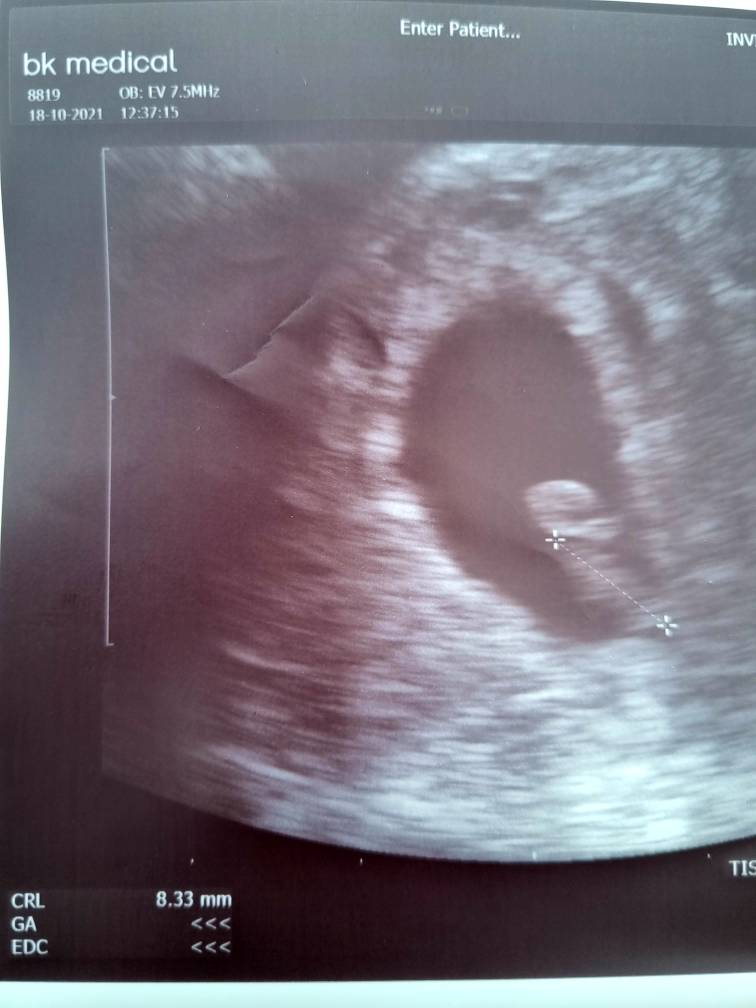

Super! Ktory tydzien jesteś?Jest serduszko [emoji3059]Zobacz załącznik 1327788

Lekarz ma sprzęt usg który nie wyznacza dni, ale powiedział ze wychodzi 6+kilka dni, a wg OM 6t3d.Super! Ktory tydzien jesteś?